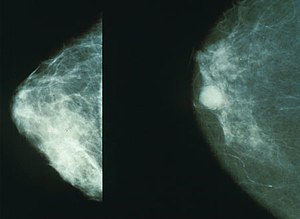

유방암은 유방에 암세포로 구성된 덩어리로 이루어진 암입니다. 유방암은 일반적으로 유방의 유관과 엽에서 발생하며, 가장 흔한 유방암 유형은 "침윤성 유관 암종"입니다. 유방암은 남성에게도 발생할 수 있지만 환자의 99%는 여성입니다. 대부분과 다르게 우리나라 통계자료의 경우 전체 암에서는 5위를 차지하고, 여성암에서는 발생률 1위를 차지하고 있습니다.

유방암을 알아차리는 가장 일반적인 방법은 유방에 덩어리 또는 만져지는 덩어리가 만져지는 것입니다. 멍울은 이전에 본 적 없는 신비한 덩어리이며, 악성이라면 단단하고 고정되어 움직이지 않으며 모양이 불규칙합니다. 모든 멍울이 악성은 아니며 양성일 수도 있으므로 의사와 정기적으로 검진을 받는 것이 중요하므로 이러한 유방암 초기증상을 그냥 지나치지 마시기 바랍니다.